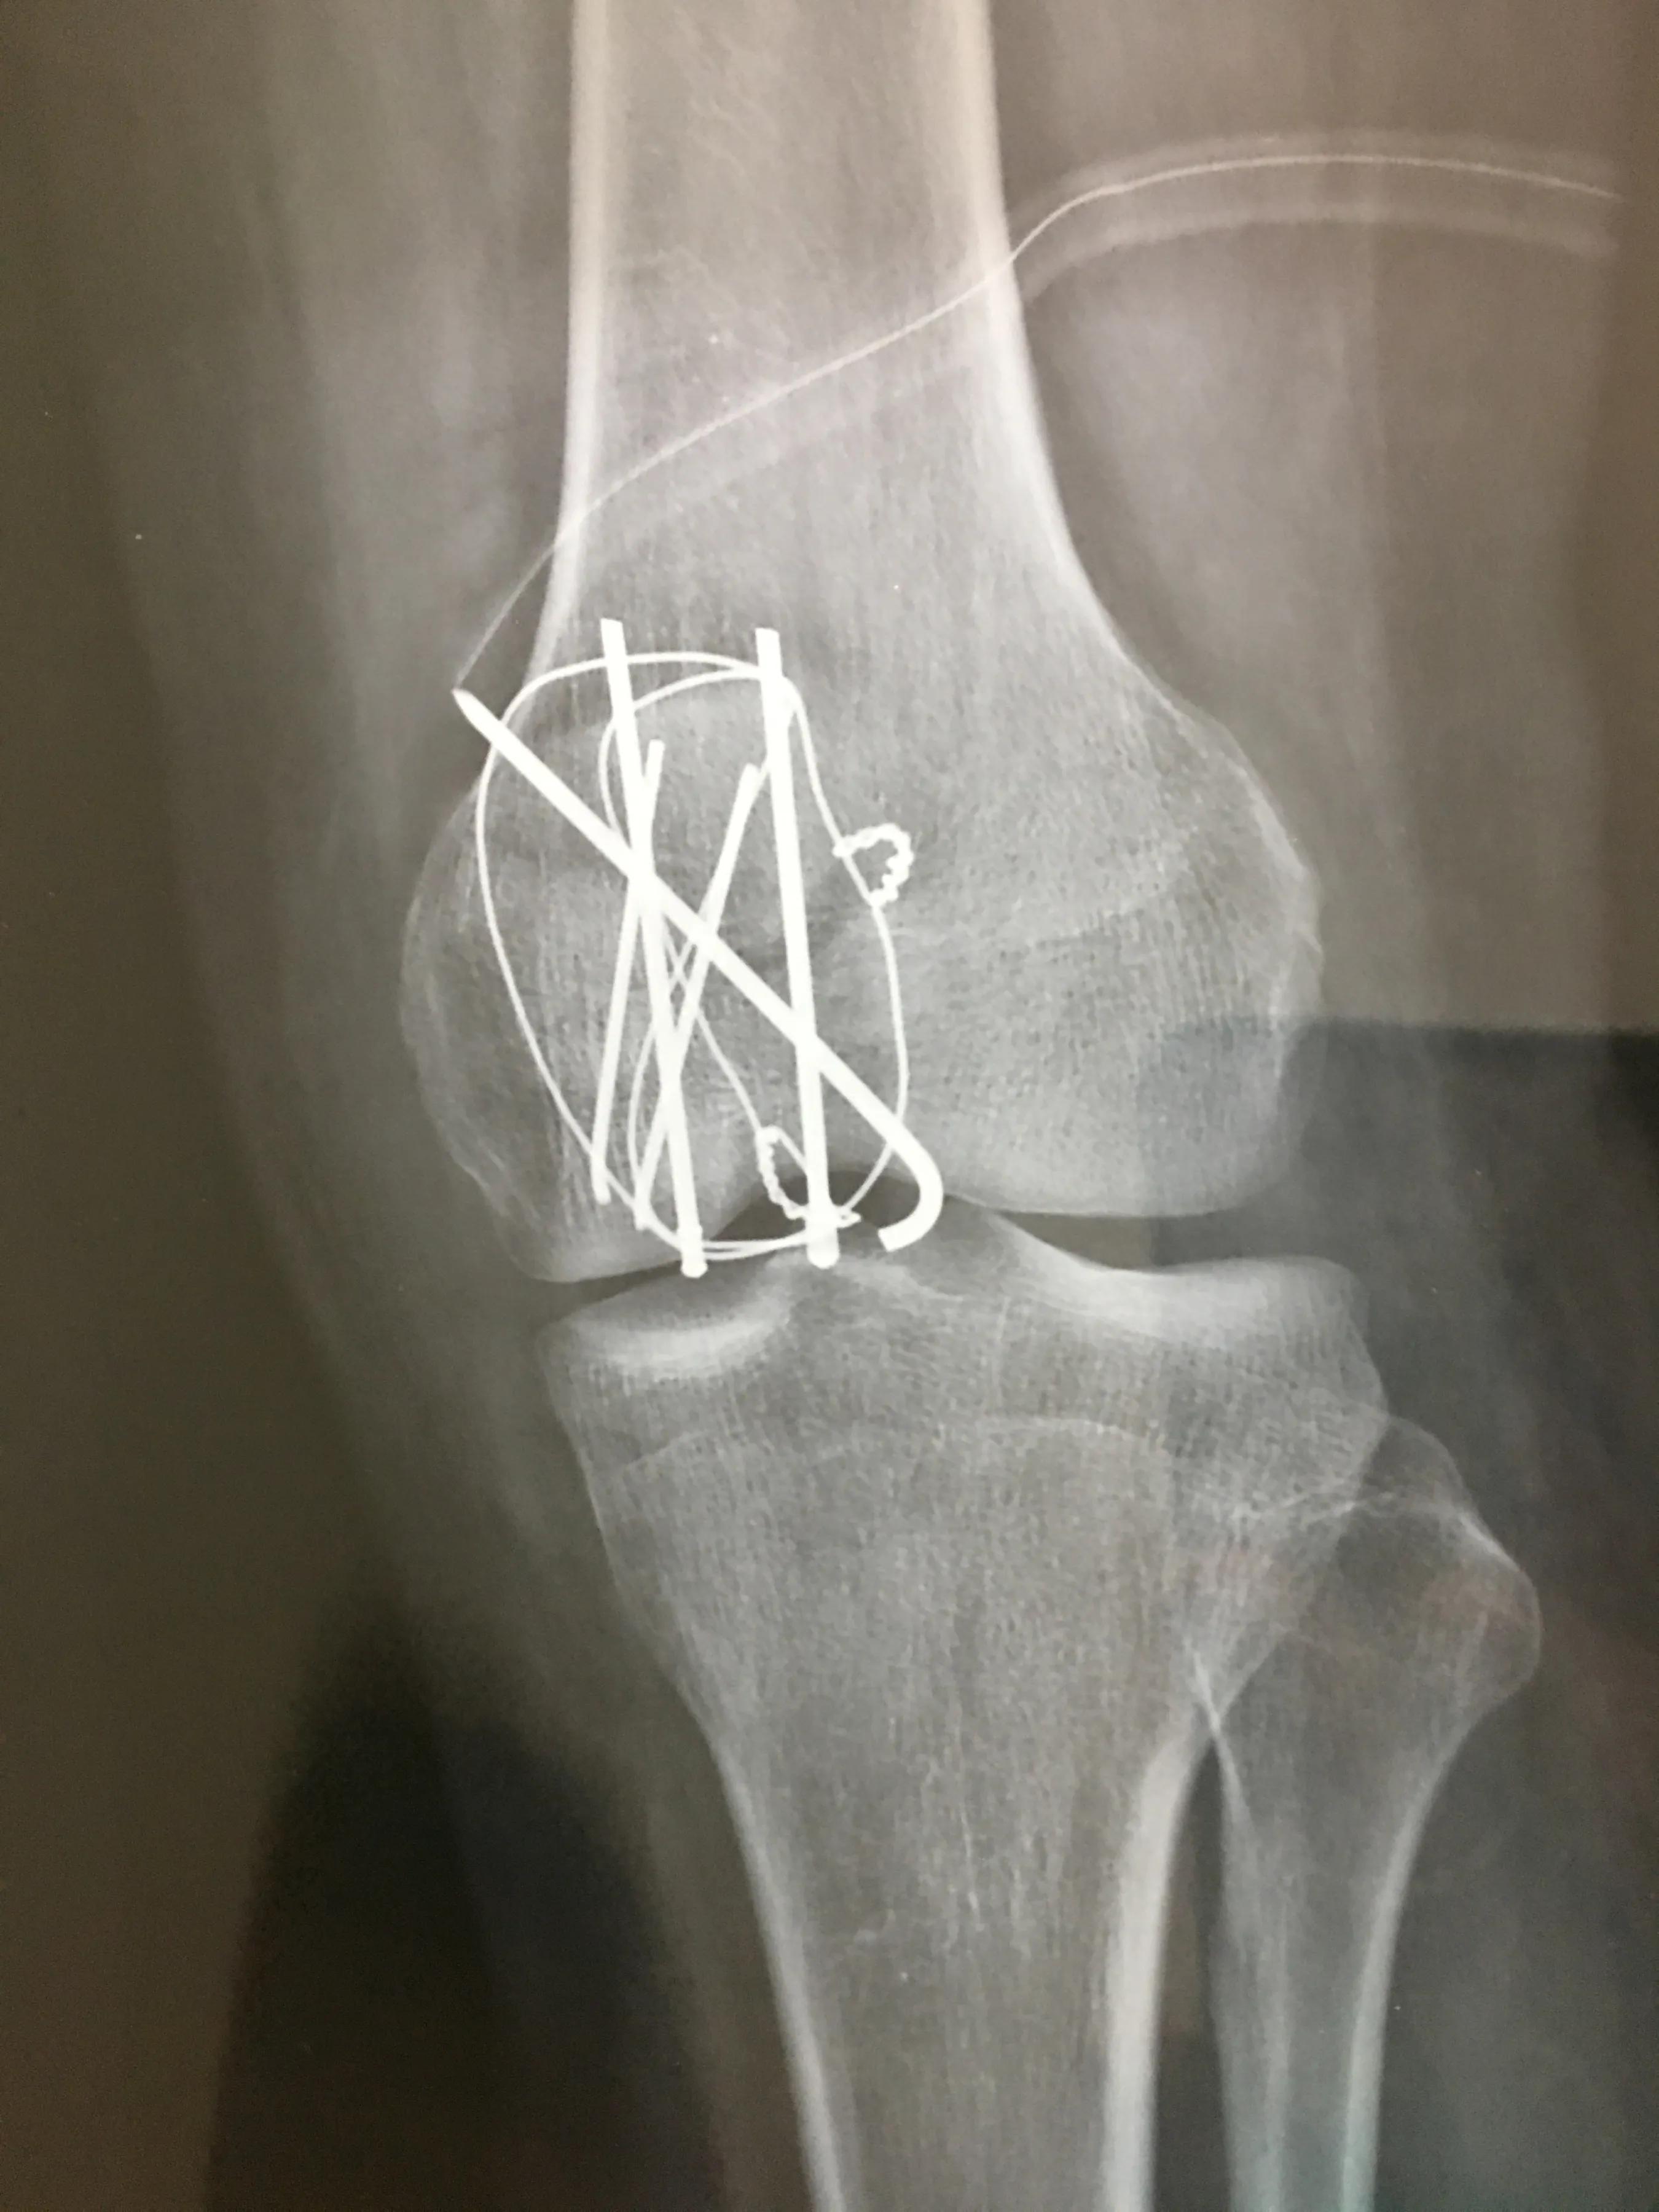

然后下午我们又赶到昆明九二零医院,挂完急诊,直接去的住院楼骨科病区,看完片子,医生说需要手术,但是现在医院没病床,先给你装一个腿下护板,回家消肿,不用吃药,因为吃不吃都是那么些天,有病床了,通知你再来。又问了一下费用,说大概一万多,报完后自费几千。当天护板费用300左右,然后就回家了。也就是从今天上护板开始,小腿就没打过弯。在家消肿前几天,膝盖肿的厉害,疼痛感不是很强烈,后来吃了大概有一瓶云南白药胶囊32粒装,明显感觉不痛了,肿也消得很快。消肿这几天,在家拄拐活动。过了大概七八天时,医生打电话,但我没接到,后来打回去才知道,病床又没有了,还得等。大概等到7月10号,来电话说来住院吧,先住胸外科,不能再等了,再等就残废了,吓得我赶紧赶到医院,当天办的住院。又开了6张需要检查的单子,这些检查有的要预约,有的排队,等全部做完,竟然用了两天的时间,又赶上周一的手术排满了,只能14号做手术。从受伤当天到做手术,中间间隔了有18天。其实这个时间有点过长,对后期恢复关节活动有一些影响的。做完手术后第四天办的出院,术后的第二天就要下地活动了,当时膝盖因为有伤口,还不能打弯,护板拆除。住院费用是一万三千多,自费不到七千。截止到今天,这次意外交给医院的总费用大概8千左右。其他花销比如吃的,用的,交通等,没算进去。

回家后,我就查了一下关节恢复的训练方法和注意事项,都说关节恢复是个漫长的过程,要提早锻炼,要有毅力。否则后期如果有粘连,还要做手术才行。从装上护板到出院中间有25天左右,小腿没有打过弯。我回到家到拆线中间的14天,每天早上都在床边靠小腿自重,压小腿,从开始的不能打弯,到现在小腿和大腿夹角能到120度左右。